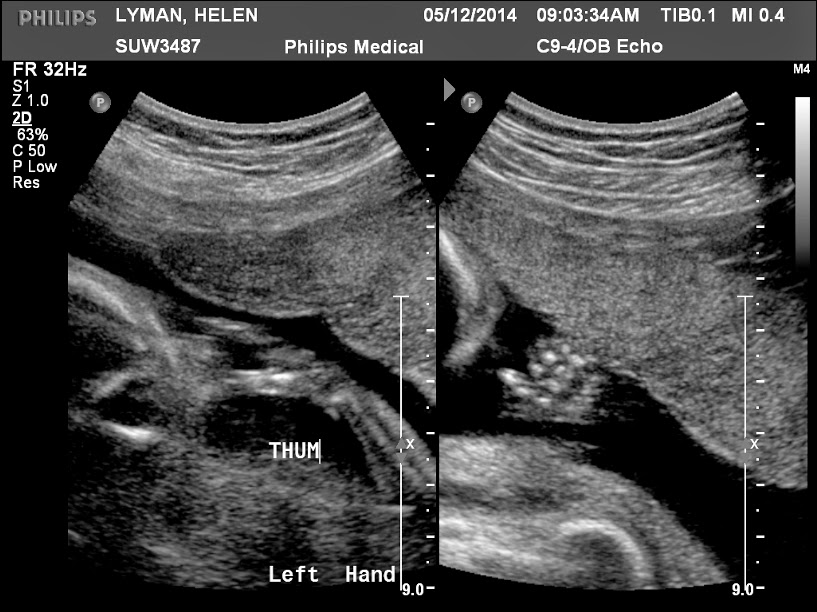

Peanut - 19 Weeks

Today we had our 19 week anatomy scan to check how peanut is developing. Perhaps we need to stop calling it peanut as it is a little bit bigger now....

Everything was fine. A good strong heart beat and everything else was present and correct and normal size - so that is a relief. For a while she kept putting her hand in front of her face making it tricky for the ultrasound specialist to measure the nose, chin and jaw, but eventually she moved it away. I say "she" as they are 90% sure that it will be a girl as there was no evidence of any boy bits...

A few scan images below....